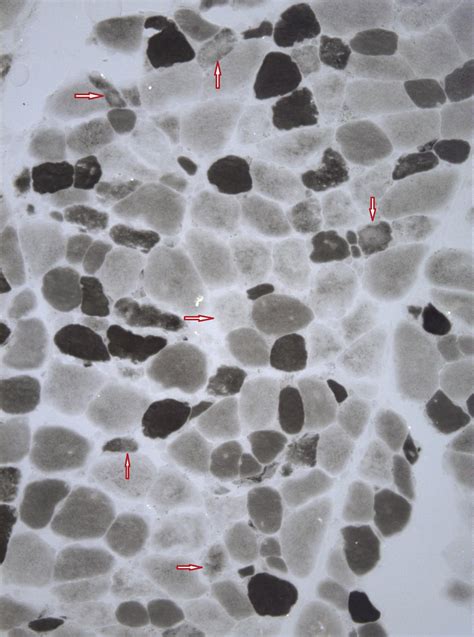

• Muscle biopsy to examine muscle tissue for signs of damage or inflammation